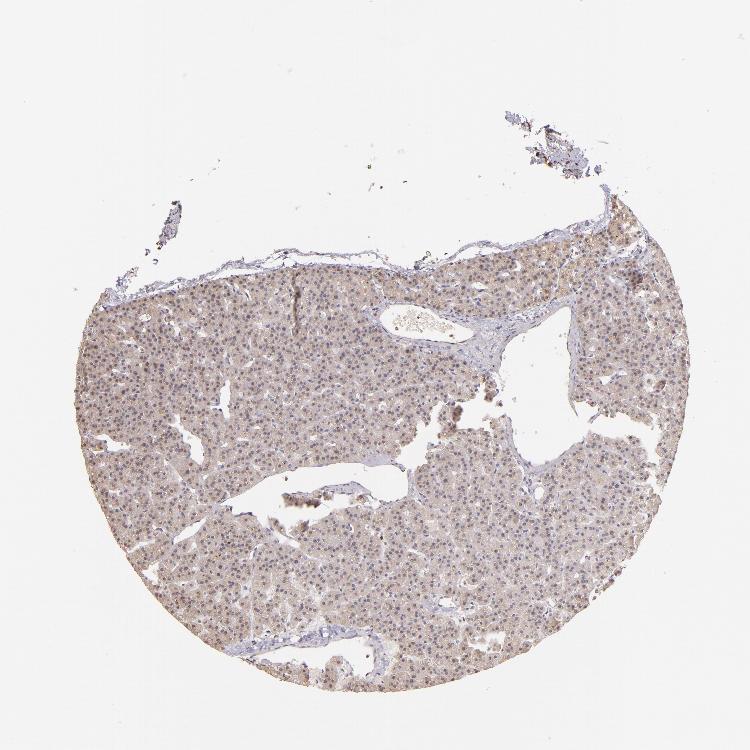

PARATHYROID GLAND - Antibody stainingi

Antibody staining in the annotated cell types in the current human tissue is reported as not detected, low, medium, or high, based on conventional immunohistochemistry profiling in selected tissues. This score is based on the combination of the staining intensity and fraction of stained cells.

Each image is clickable and will lead to virtual microscopy that enables deeper exploration of all samples and also displays staining intensity scores, fraction scores and subcellular localization as well as patient and tissue information for each sample.

Antibody HPA003134Antibody CAB002625

Glandular cells Not detectedLow